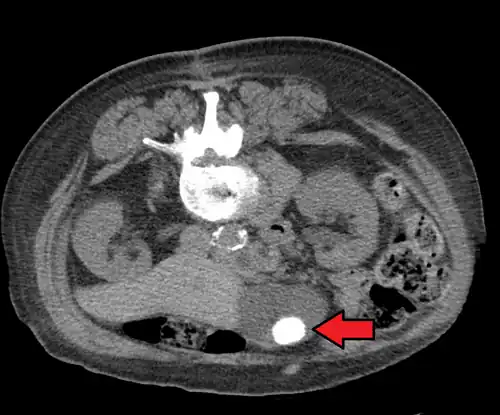

Diagnosis is typically confirmed by abdominal ultrasound. Other imaging techniques used are ERCP and MRCP. Gallstone complications may be detected on blood tests.[2]

On abdominal ultrasound, sinking gallstones usually have posterior acoustic shadowing. In floating gallstones, reverberation echoes (or comet-tail artifact) is seen instead in a clinical condition called adenomyomatosis. Another sign is wall-echo-shadow (WES) triad (or double-arc shadow) which is also characteristic of gallstones.[43]